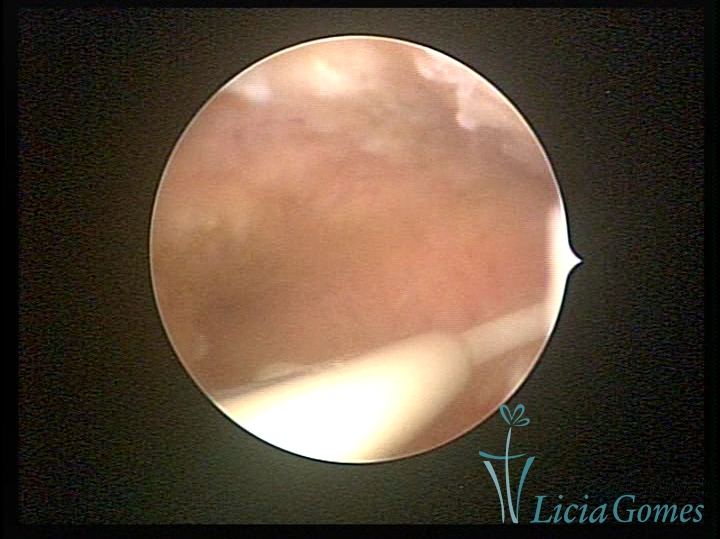

Cavidade uterina com DIU normoposicionado